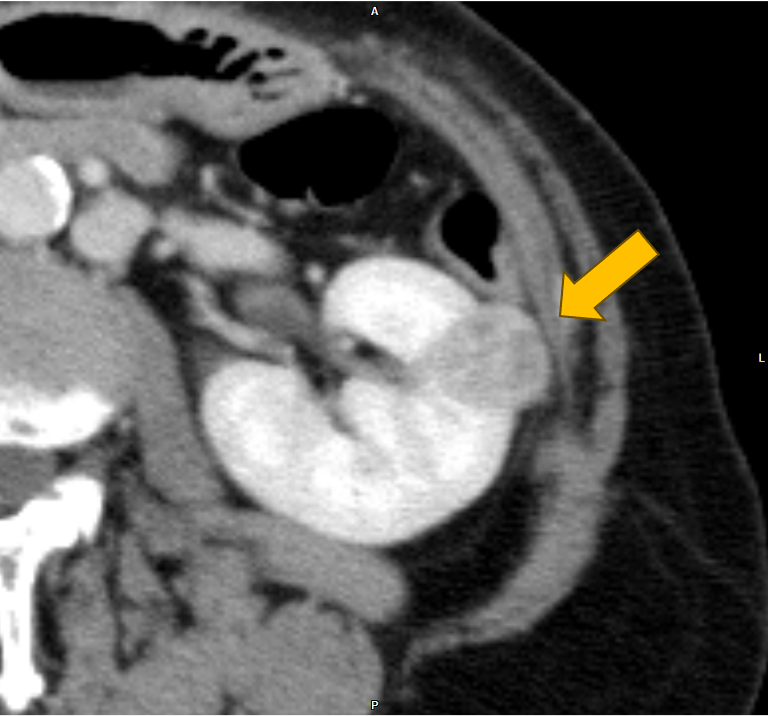

右腎癌(淡明細胞型腎細胞癌)術後の経過観察中に、左腎、膵尾部、胸骨の腫瘍が明らかとなり、胸骨病変の組織診断により右腎癌の転移の確定診断となった。本CTは化学療法中の治療効果判定目的に施行された腎ダイナミック造影CTである。

当該疾患の診断における造影CTの役割

右腎癌術後(淡明細胞型腎細胞癌)、左腎、膵体部、胸骨背側に腫瘤を認める。造影CTにおいての膵実質との増強効果の違いにより膵腫瘍を描出することができる。膵腫瘤はDynamic造影で早期濃染色、washoutパターンを呈しており、乏血性の造影パターンを呈す通常の膵癌との鑑別は容易である。